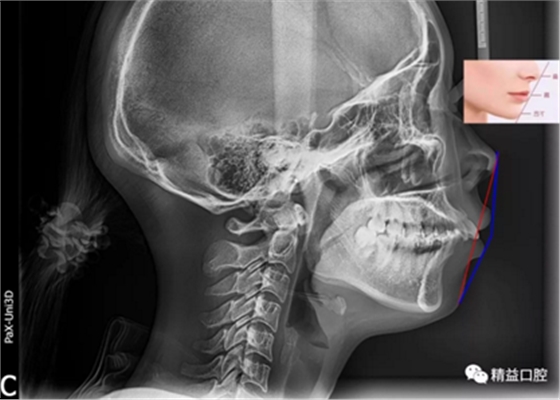

矯正前頭顱側(cè)位片

嘴唇突度非常明顯,后期經(jīng)過測量,發(fā)現(xiàn)是典型的安氏II類加骨性II類,齙牙前突。

矯正前后面部對比圖,不僅改善了嘴凸的問題,最最重要的是

下巴!下巴!下巴!一條完美的曲線正從我們眼前劃過~~~